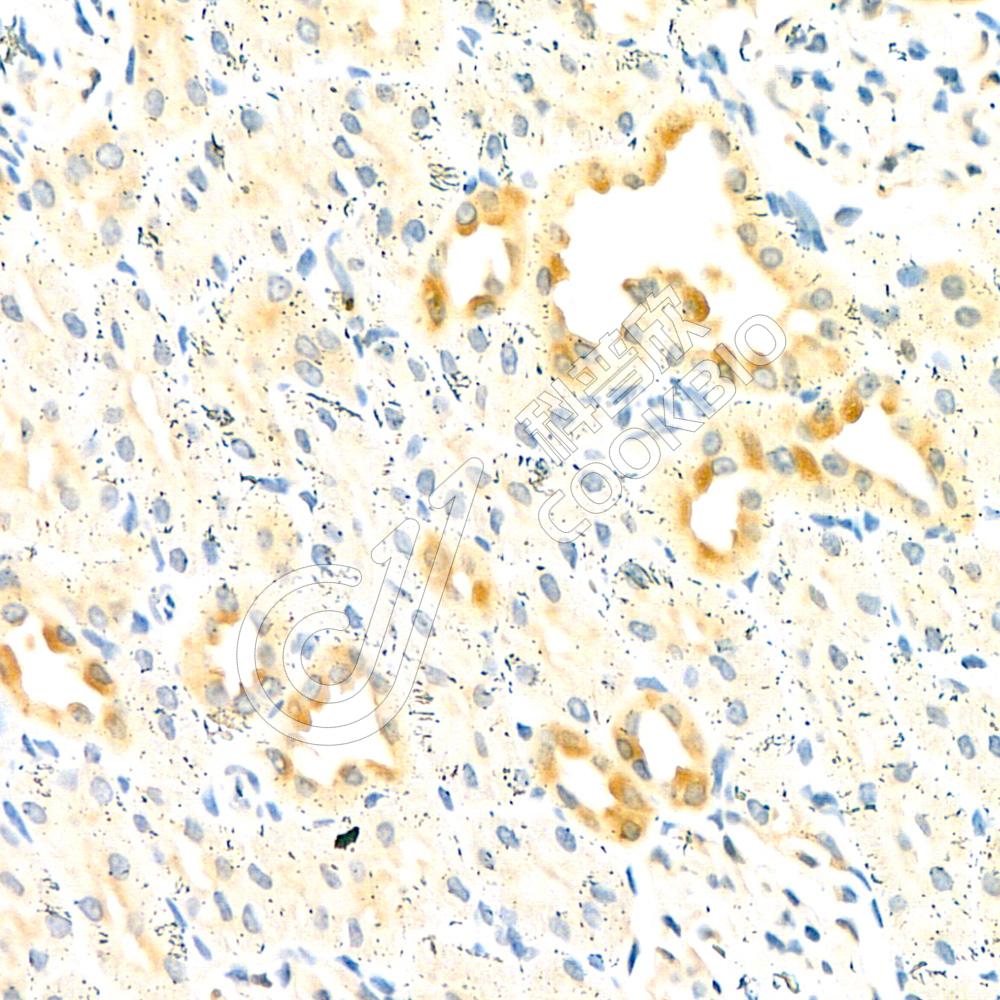

IHC检测Dmac2l蛋白(货号 K1336849).

样品: 小鼠LPS诱导的脓毒症模型肾, 4%多聚甲醛 (货号KSG1101) 固定12-24小时.

抗原修复: 柠檬酸抗原修复液(干粉, pH 6.0) (KSG1201), 98℃, 20分钟.

—抗: 1: 800稀释, 4℃ 孵育过夜.

二抗: S-vision免疫组化多聚二抗(山羊抗兔),即用型 (货号KB3906), 室温孵育20分钟.

样品: 大鼠肾, 4%多聚甲醛 (货号KSG1101) 固定12-24小时.